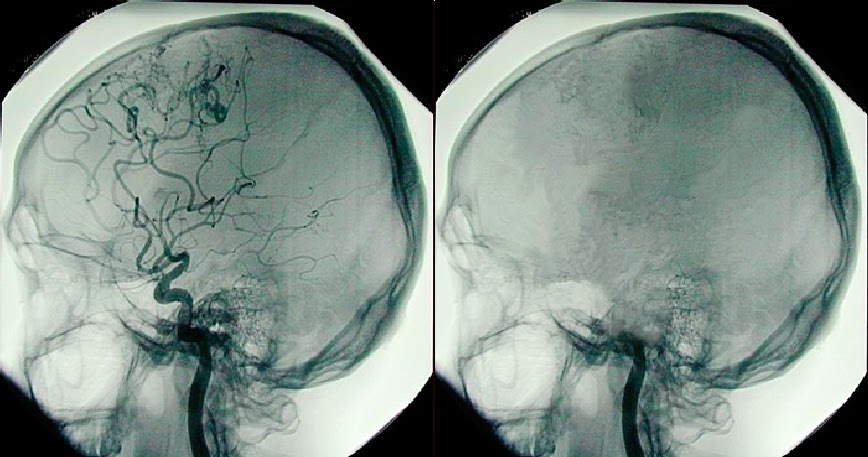

Спустя еще неделю, 22 декабря 2013 по приглашению того же судьи, что дал охранный ордер приходит независимый эксперт — профессор, завотделением детской неврологии очень авторитетного заведения - Школы медицины при Стендфордском университете Paul Graham Fisher. А также родители девочки вызывают известного в стране педиатра Paul A. Byrne, который по странному стечению обстоятельств поддерживает идею, что смерть мозга не является смертью всего организма. Они подтверждают смерть мозга. На энцефалограмме прямые линии, на ангиограмме кровообращения нет ни в одном из отделов мозга, пациентка даже не пытается дышать при отключении ИВЛ. И 24 декабря Суд признает девочку официально покойной и постановляет отключить уже тело от систем жизнеобеспечения, как только истечет охранный ордер от предыдущих юристов.

Июль 2014. У девочки, которой уже исполнилось 13 лет, начинаются регулярные менструации. Тут всем уже становится интересно: для этого гипоталамус должен работать и вырабатывать определенные гормоны. Энцефалограмма и ангиограмма по-прежнему показывают смерть всех отделов мозга.